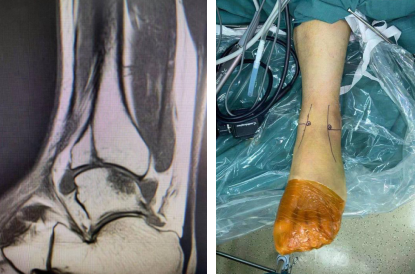

病例一:患者为23岁男性,6天前干活时扭伤左踝,导致左前踝骨折合并距腓前韧带损伤。

2月3日,石院长曹广超主任胡帆医生团队为患者进行了关节镜下左踝关节清理、机器人辅助下左前踝骨折复位内固定、左距腓前韧带修复术。术中,关节镜探查见踝关节大量血肿及充血滑膜,左前踝骨折处向上移位,踝关节不稳;手法复位外踝骨折断端,机器人辅助定位,克氏针临时固定,透视见复位满意,以2枚螺钉固定,再次透视见骨折断端对位对线良好,骨折复位良好。

术前CT

术前MRI(左图),术中设计(右图)